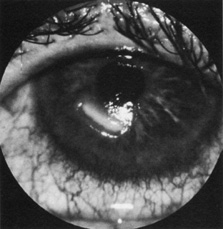

Neuroparalytic keratitis or widespread loss of corneal epithelium may occur in an eye that becomes denervated (Fig. 6). The etiology of the keratopathy is unknown, but it is presumed that loss of sensory innervation impairs corneal nutrition, surface maintenance, and repair.16,17 The keratopathy may respond poorly to artificial tear preparation and bandage soft contact lenses, but often the epithelial defect will heal after a tarsorrhaphy, which better protects the corneal epithethelium.18

Fig. 6. Neurotrophic ulcer of a denervated cornea.